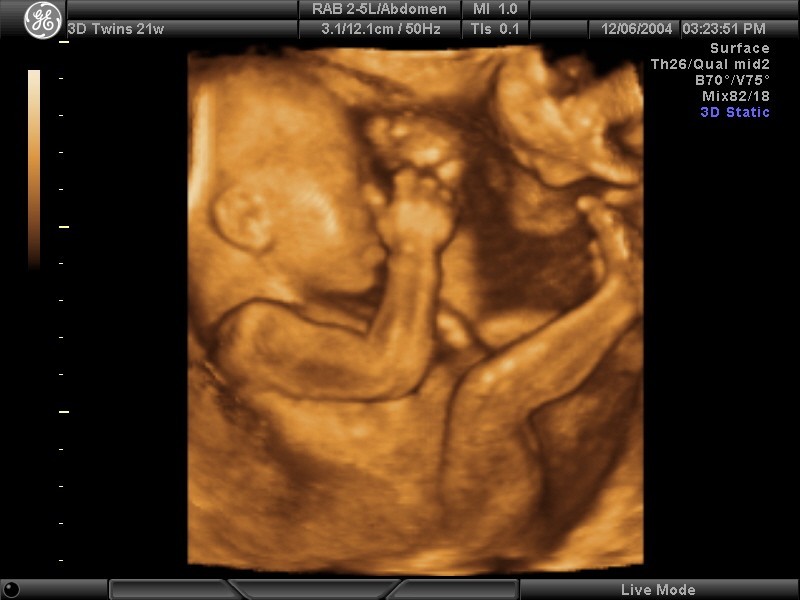

Фото Плода На 21